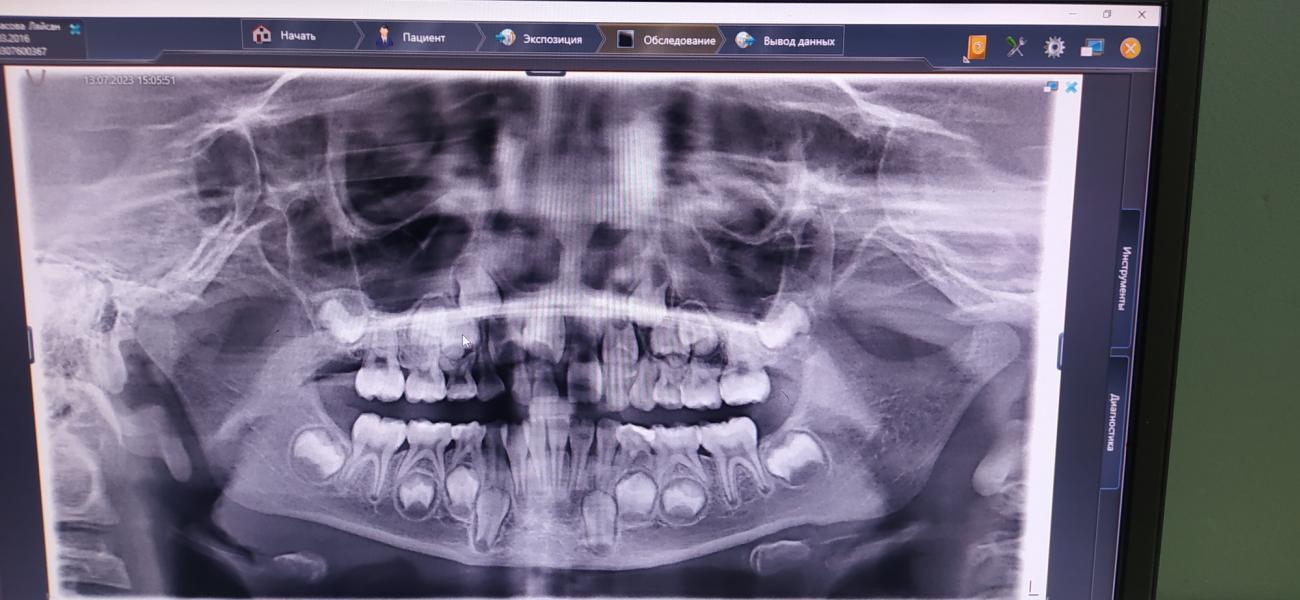

Да, можно вытолкать. Но у нас там сложнее ситуация. Специально делали панорамный снимок

У дочи криво выросли три постоянных зуба. Один прям заметно криво,видно по фото. Меня стало это сильно беспокоить. Хоть меня все близкие отговаривали, что всё само по себе исправится, когда все зубы сменятся. Но я не смогла спокойно ждать и сводила к ортодонту. Нам сделали снимок и сказали надо исправлять сейчас,пока не поздно. Пошла лёгкая ассиметрия лица вправо🥹

И зуб, особенно тот, что сильно кривой,уже не встанет на место сам. Либо сейчас исправлять, либо в будущем брекеты. Если не исправить сейчас,то возникнут сложности с прикусом, ассиметрия лица и возможно логопедические проблемы...

У Ляйсан долго сменяются зубы,ей 7,а выпали только 3 ,удалили тоже 3. Удаляли из-за того, что постоянные росли за молочными. Долгая смена зубов это плохо тем,что это болезненно и зубы растут криво. Надо давать ребенку твердую еду и стимулировать десна щёткой или пальцами.